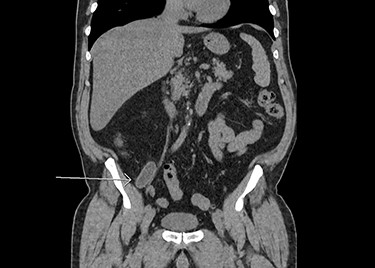

A 72-year-old man was referred to the emergency room (ER) by his physician for a 48-hour abdominal pain. The pain was located in the left upper quadrant and was characterized as initially transfixing but had mostly subsided by the time the patient consulted to the ER. The patient’s medical record was significant for an iatrogenic hypothyroidism, a right inguinal herniorrhaphy and two negative colonoscopies. The physical examination showed a soft abdomen and no fever. The total white blood cells count was 13.0 × 109. A computed tomography (CT) scan was performed and revealed an enlarged appendix filled with liquid with surrounding fat stranding compatible with an acute appendicitis, although a mucocele could not be excluded (see Fig. 1).